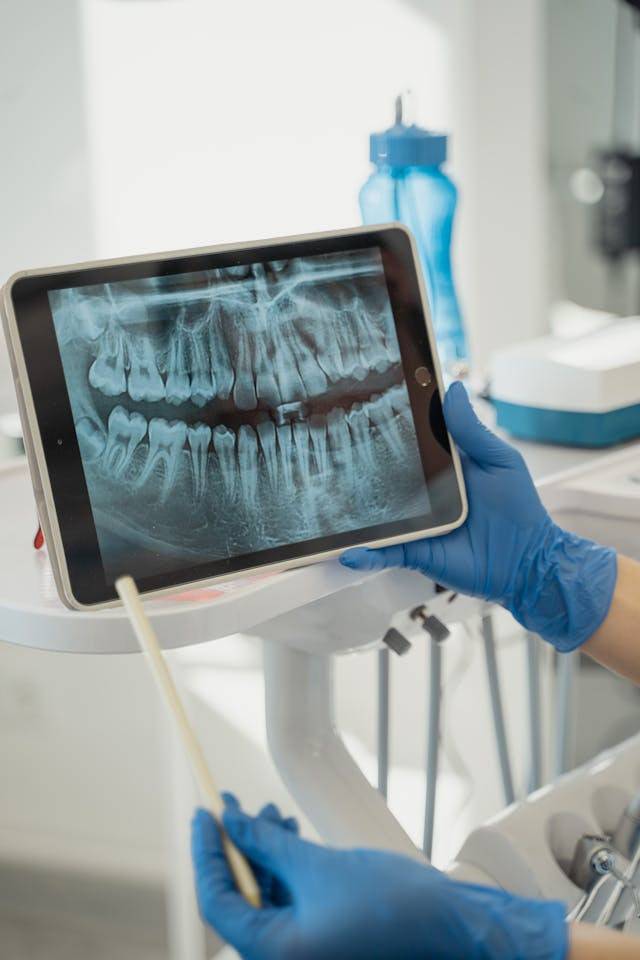

심지어 턱관절이

머리 무게를 지탱하면서

염증과 통증을 유발하고

심한 경우엔

턱관절 변형까지 온다는데요